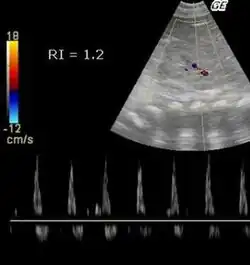

Индекс резистентности (ИР; англ. RI, resistance/resistive index или индекс Пурсело англ. Pourcelot Resistive Index) — отражает разницу между фазами сердечного цикла (систолой и диастолой). Чем выше индекс, тем больше разница. Используется для оценки сосудистой гемодинамики.

| 1 | Систолический кровоток, диастолический кровоток отсутствует |

| >1 | Обратный ток крови во время диастолы |

После трансплантации почки у пациентов с RI> 0,8 наблюдается повышенная смертность.